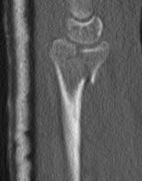

Radial styloid fractures / Chauffeur's Fracture

Associations

Perilunate fracture / dislocations

Radiocarpal dislocation

Scaphoid fractures

Options

K wires / screw fixation / radial styloid plate / volar locking plate